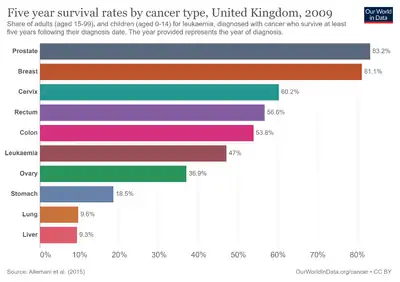

Many cases are managed with active surveillance or watchful waiting.[3] Other treatments may include a combination of surgery, radiation therapy, hormone therapy or chemotherapy.[3] When it only occurs inside the prostate, it may be curable.[2] In those in whom the disease has spread to the bones, pain medications, bisphosphonates and targeted therapy, among others, may be useful.[3] Outcomes depend on a person's age and other health problems as well as how aggressive and extensive the cancer is.[3] Most men with prostate cancer do not end up dying from the disease.[3] The 5-year survival rate in the United States is 98%.[5] Globally, it is the second most common type of cancer and the fifth leading cause of cancer-related death in men.[18] In 2018, it occurred in 1.2 million men and caused 359,000 deaths.[6] It was the most common cancer in males in 84 countries,[4] occurring more commonly in the developed world.[19] Rates have been increasing in the developing world.[19] Detection increased significantly in the 1980s and 1990s in many areas due to increased PSA testing.[4] Studies of males who died from unrelated causes have found prostate cancer in 30% to 70% of those over age 60.[2]

Prognosis

Many prostate cancers are not destined to be lethal, and most men will ultimately not die as a result of the disease. Mortality varies widely across geography and other elements. In the United States, five-year survival rates range from 29% (distant metastases) 100% (local or regional tumors).[157] In Japan, the fatality rate rose to 8.6/100,000 in 2000.[158] In India in the 1990s, half of those diagnosed with local cancer died within 19 years.[159] One study reported that African-Americans have 50–60 times more deaths than found in Shanghai, China.[160] In Nigeria, 2% of men develop prostate cancer, and 64% of them are dead after 2 years.[161] Most Nigerian men present with metastatic disease with a typical survival of 40 months.[162]

Epidemiology

As of 2012, prostate cancer is the second-most frequently diagnosed cancer (at 15% of all male cancers)[177] and the sixth leading cause of cancer death in males worldwide.[178] In 2010, prostate cancer resulted in 256,000 deaths, up from 156,000 deaths in 1990.[179] Rates of prostate cancer vary widely across the world. Although the rates vary widely between countries, it is least common in South and East Asia, and more common in Europe, North America, Australia, and New Zealand.[180] Prostate cancer is least common among Asian men and most common among black men, with figures for white men in between.[181][182]

In 2018, an estimated 164,690 new cases and 29,430 prostate cancer–related deaths will occur in the United States. Prostate cancer is now the second-leading cause of cancer death in men, exceeded by lung cancer and colorectal cancer. It accounts for 19% of all male cancers and 9% of male cancer-related deaths. Age-adjusted incidence rates increased steadily from 1975 through 1992, with particularly dramatic increases associated with the inception of widespread use of prostate-specific antigen (PSA) screening in the late 1980s and early 1990s, followed by a fall in incidence. A decline in early-stage prostate cancer incidence rates from 2011 to 2012 (19%) in men aged 50 years and older persisted through 2013 (6%).

Between 2013 and 2015, mortality rates appear to have stabilized. Declines in mortality rates in certain jurisdictions may reflect the benefit of PSA screening, but these observations may be explained by independent phenomena such as improved treatments. The estimated lifetime risk of a prostate cancer diagnosis is about 14.0%, and the lifetime risk of dying from this disease is 2.6%. Cancer statistics from the American Cancer Society and the National Cancer Institute indicated that between 2005 and 2011, the proportion of disease diagnosed at a locoregional stage was 93% for whites and 92% for African Americans; the proportion of disease diagnosed at a late stage was 4% for whites and 5% for African Americans.

People with prostate cancer generally encounter significant disparities in awareness, funding, media coverage, and research—and therefore, inferior treatment and poorer outcomes—compared to other cancers of equal prevalence.[205] In 2001, The Guardian noted that Britain had 3,000 nurses specializing in breast cancer, compared to only one for prostate cancer. It also discovered that the waiting time between referral and diagnosis was two weeks for breast cancer but three months for prostate cancer.[206]

A 2007 report by the U.S.-based National Prostate Cancer Coalition stated that for every prostate cancer drug on the market, there were seven used to treat breast cancer. The Times also noted an "anti-male bias in cancer funding" with a four-to-one discrepancy in the United Kingdom by both the government and by cancer charities such as Cancer Research UK.[205][207] Equality campaigners such as author Warren Farrell cite such stark spending inequalities as a clear example of governments unfairly favouring women's health over men's health.[208]

Disparities also extend into areas such as detection, with governments failing to fund or mandate prostate cancer screening while fully supporting breast cancer programs. For example, a 2007 report found 49 U.S. states mandate insurance coverage for routine breast cancer screening, compared to 28 for prostate cancer.[209] Prostate cancer also experiences significantly less media coverage than other, equally prevalent cancers, with a study by Prostate Coalition showing 2.6 breast cancer stories for each one covering cancer of the prostate.[205]